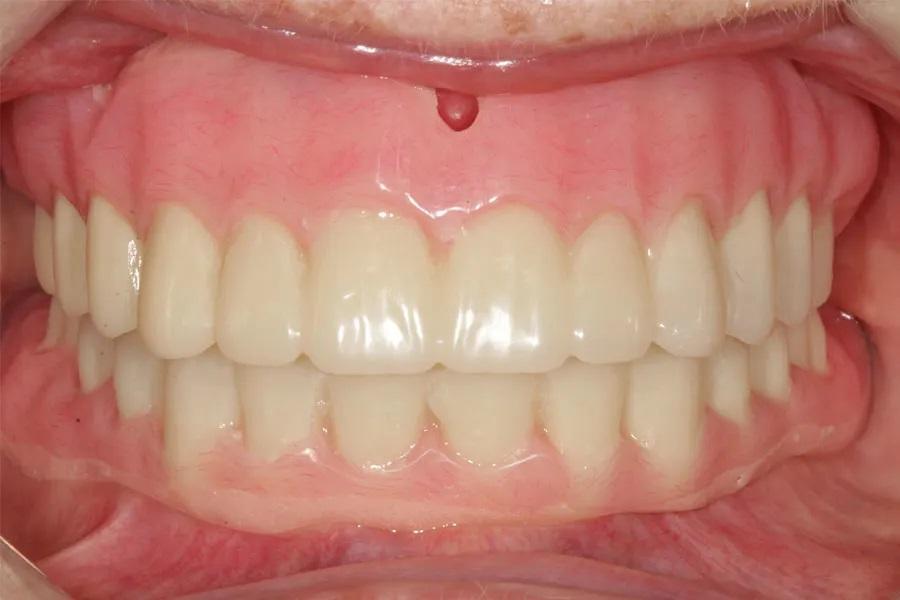

Фото 8: Окончательные протезы.

Фото 9: Установка протезов. Пациентка довольна эстетическим и функциональным результатом.

Пациентка осталась довольна результатом, отметила уменьшение страха перед стоматологией и рассматривала возможность установки имплантатов для покрывного протеза нижней челюсти. Она также с энтузиазмом оценила сокращение количества визитов и снижение риска инфицирования. Протезы имели отличную посадку, стабильную окклюзию и удовлетворительную эстетику. Пациентка была рада, что у нее есть копия протезов на случай чрезвычайной ситуации.